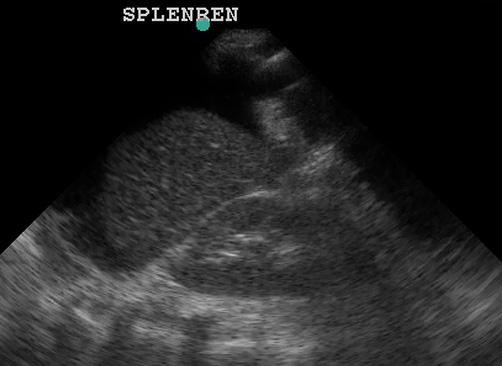

In the normal scan, the spleen and kidney are tightly juxtaposed, with a hyperechoic line separating them. The diaphragm is the echogenic line just cephalad to the spleen.

(Figure 30/30.1)